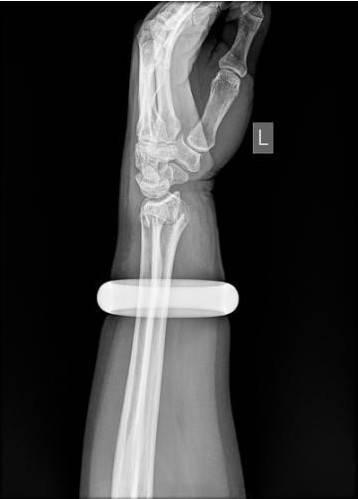

雪天摔倒手腕骨折,在邻居建议下跑去按摩,不料手腕越肿越厉害,2万元玉镯深陷肉里。为保住手臂,王阿姨“狠心”砸碎玉镯,顺利接受了手法复位。

25日早上,57岁的王女士买菜回家时不慎滑倒,情急之下她用左手撑地,很快手腕就肿了起来。邻居听说后,让她赶紧去做做按摩,结果越按越痛,越肿越厉害。下午她找到武汉市第一医院骨科门诊,拍片发现左手桡骨远端骨折。

此时,手镯卡住腕部,不但会加重局部肿胀,还会越勒越紧导致肢体坏死。管床医生石晨尝试用肥皂水、润滑剂等方法取镯,都没能成功。

玉镯贴身戴了七八年,当年花了2万元买的。思虑再三,王女士提出砸碎玉镯,并签字为证。石晨用叩诊锤敲碎了镯子后,当即为她手法复位,打上了石膏。

26日上午,该院骨科病房还收治了一位48岁的女患者,也是左臂骨折,戴着玉镯的她第一时间赶到医院,医生趁着肿胀不是太厉害,赶紧将镯子取下来。